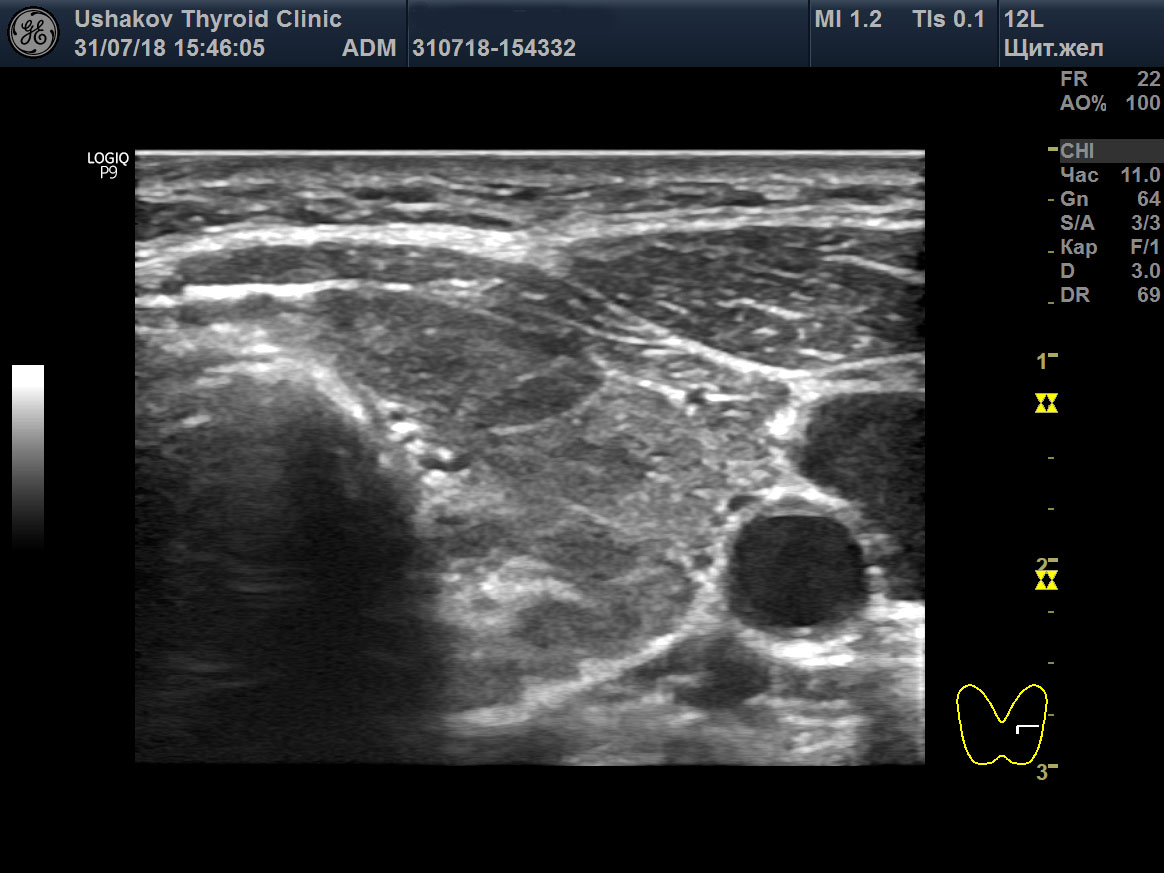

Основой УЗИ Щитовидной Железы (УЗИ ЩЖ) является серая шкала или В-режим. Он выглядит так:

УЗИ ЩЖ в серой шкале. посмотрите - в доле видны деление (белыми линиями) на части - сегменты.

Черно-белая (серая) шкала УЗИ ЩЖ позволяет изучать строение и изменение структуры железы и окружающих образований. Но она очень мало сообщает о функциональном состоянии железы.